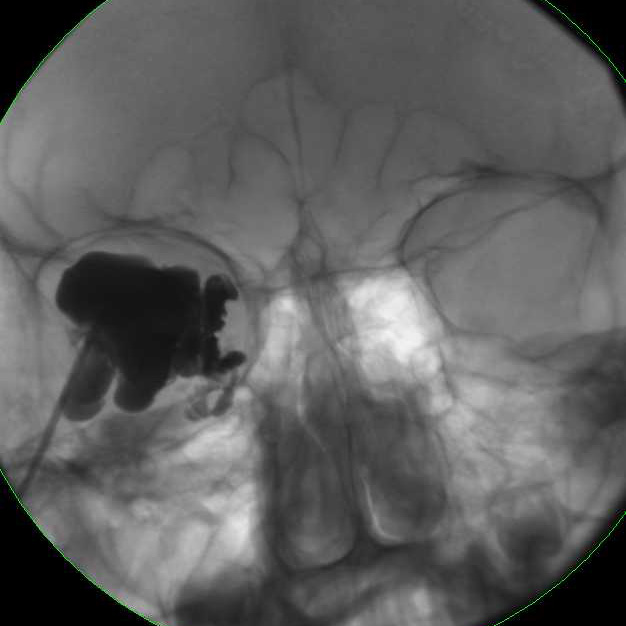

MRI of large LM cyst (top), catheter passing through lower lid (left), cystogram (right).